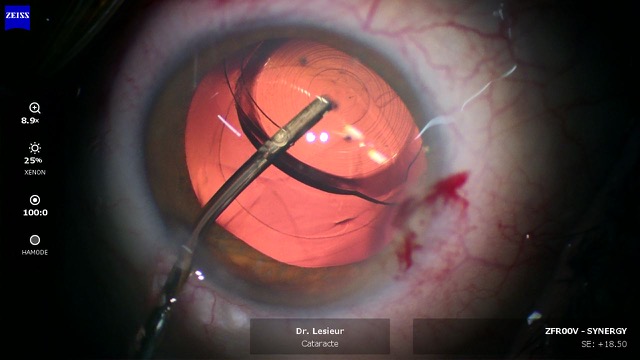

Retrait du cristallin

Le cristallin est fragmenté par ultrasons (phacoémulsification) puis aspiré délicatement. Cette technique éprouvée permet un retrait complet tout en préservant l'enveloppe du cristallin, qui servira de support à l'implant.

Pose de l'implant

L'implant intraoculaire, plié sur lui-même, est introduit par la micro-incision. Il se déploie à l'intérieur de l'œil et se positionne exactement à l'emplacement de l'ancien cristallin. Son centrage est vérifié avec précision.